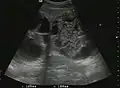

The ultrasound appearance is a well defined lesion, with very thin, almost unapparent walls, without circulatory signal at Doppler or CEUS investigation. The content is transonic suggesting fluid composition. The presence of membranes, abundant sediment or cysts inside is suggestive for parasitic, hydatid nature. Posterior from the lesion the acoustic enhancement phenomenon is seen, which strengthens the suspicion of fluid mass. They typically displace normal liver vessels but no vascular or biliary invasion occurs.

Hydatid liver cyst. Diagnostic criteria are the presence of membranes and sediment inside.